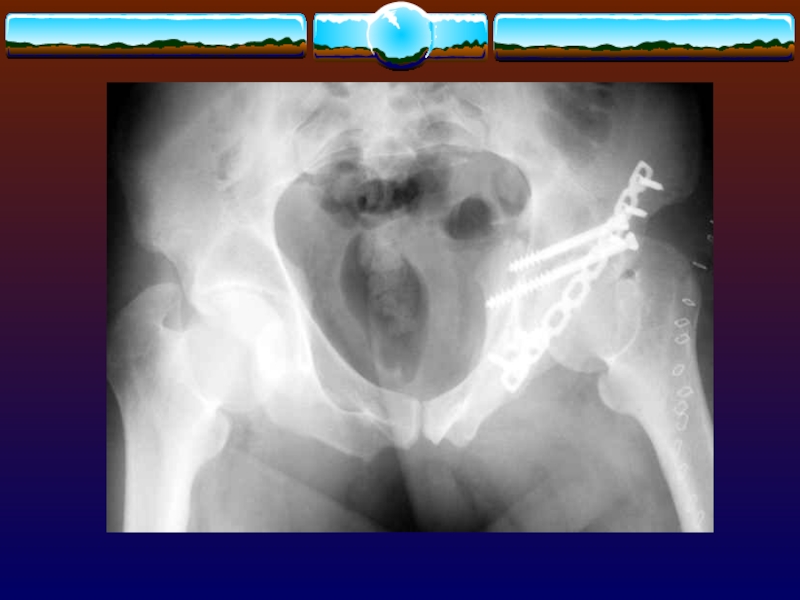

Слайд 109Квалифицированная медицинская помощь

Стабилизация таза.

При повреждении внутренних органов –оперативное лечение.

При повреждении

мочевого пузыря, уретры - наложение надлобкового свища.

При повреждении прямой кишки-непременно

накладывается противоестественный задний проход.

Квалифицированная медицинская помощь Стабилизация таза.При повреждении внутренних органов –оперативное лечение.При повреждении мочевого пузыря, уретры - наложение надлобкового

Слайд 110Методики наружной фиксации

Стержневой аппарат

Тазовый зажим Gaza

Методики наружной фиксации Стержневой аппарат Тазовый зажим Gaza